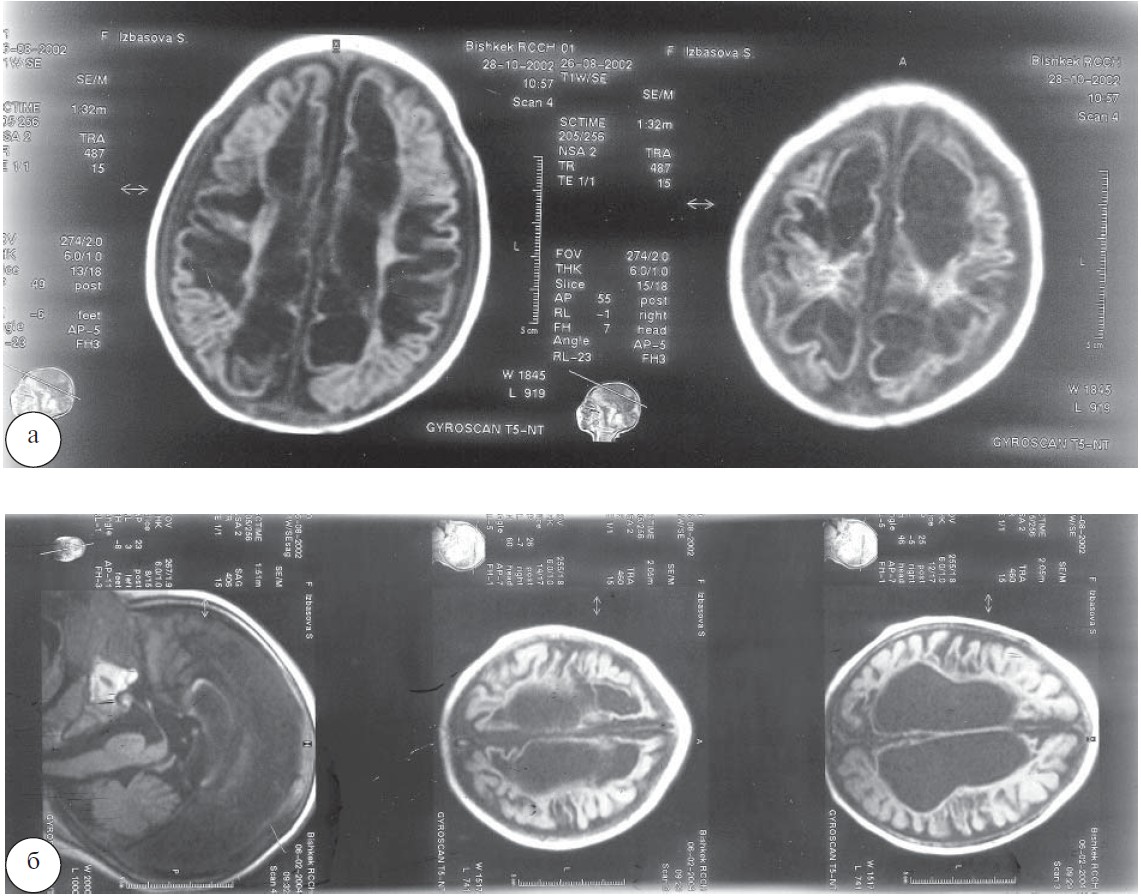

Эффективность лечения воспалительных заболеваний мозга представлена на примере лечения туберкулезного менингита (рис. 1), сирингомиелии (рис. 2, 3), перинатальной энцефалопатии и гидроцефалии (рис. 4), нейропатии лицевого нерва (рис. 5, 6) [12-15, 17].

Рис. 1. Особенности течения туберкулезного процесса в центральной нервной системе: а — больные группы сравнения; б — больные основной группы.

Рис. 4. МРТ головного мозга ребенка С., возраст 1 год 3 месяца, девочка. Диагноз — перинатальная энцефалопатия, гидроцефалия: а — в течение 6 месяцев лечилась по стандартным схемам, включая мочегонную терапию; б — через 2 месяца после проведения 3 курсов непрямой стимуляции лимфодренажного механизма нервной системы.